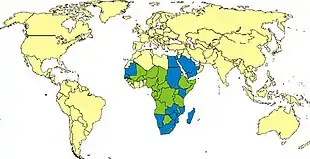

| Frequency | Outbreaks in Africa and Arabia[1] |

Outbreaks of the disease have only occurred in Africa and Arabia. Outbreaks usually occur during periods of increased rain which increase the number of mosquitoes.[1] The disease was first reported among livestock in Rift Valley of Kenya in the early 1900s,[2] and the virus was first isolated in 1931.[1]

RVF outbreaks occur across sub-Saharan Africa, with outbreaks occurring elsewhere infrequently. Outbreaks of this disease usually correspond with the warm phases of the EI Niño/Southern Oscillation. During this time there is an increase in rainfall, flooding and greenness of vegetation index, which leads to an increase in mosquito vectors.[22] RVFV can be transmitted vertically in mosquitos, meaning that the virus can be passed from the mother to her offspring. During dry conditions, the virus can remain viable for a number of years in the egg. Mosquitos lay their eggs in water, where they eventually hatch. As water is essential for mosquito eggs to hatch, rainfall and flooding cause an increase in the mosquito population and an increased potential for the virus.[23]

The first documented outbreak was identified in Kenya in 1931, in sheep, cattle and humans;[24] another severe outbreak in the country in 1950–1951 involved 100,000 deaths in livestock and an unrecorded number of humans with fever.[25] An outbreak occurred in South Africa in 1974–1976, with more than 500,000 infected animals and the first deaths in humans.[26][27] In Egypt in 1977–78, an estimated 200,000 people were infected and there were at least 594 deaths.[28][29] In Kenya in 1998, the virus killed more than 400 people. Since then, there have been outbreaks in Saudi Arabia and Yemen (2000), East Africa (2006–2007),[30] Sudan (2007),[31] South Africa (2010),[32][33] Uganda (2016),[34] Kenya (2018),[35] and Mayotte (2018–2019).[36] 2020–2021 in Kenya,[37] in 2022 an outbreak is ongoing in Burundi.